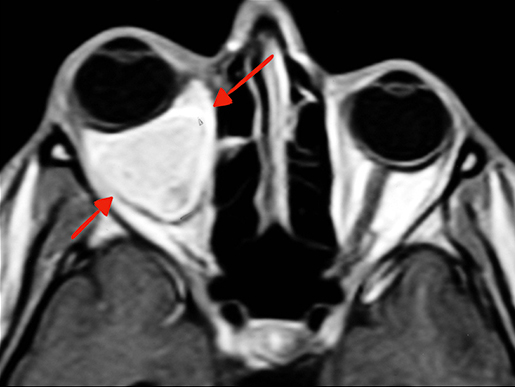

- εκτός, διά του σφηνουπερώιου τρήματος στον υποκροτάφιο βόθρο και διά της υποκογχίου σχισμής προς τον οφθαλμικό κόγχο,

- Στάδιο C1: διήθηση του πτερυγο-υπερώιου, του υποκροταφίου βόθρου και του οφθαλμικού κόγχου,